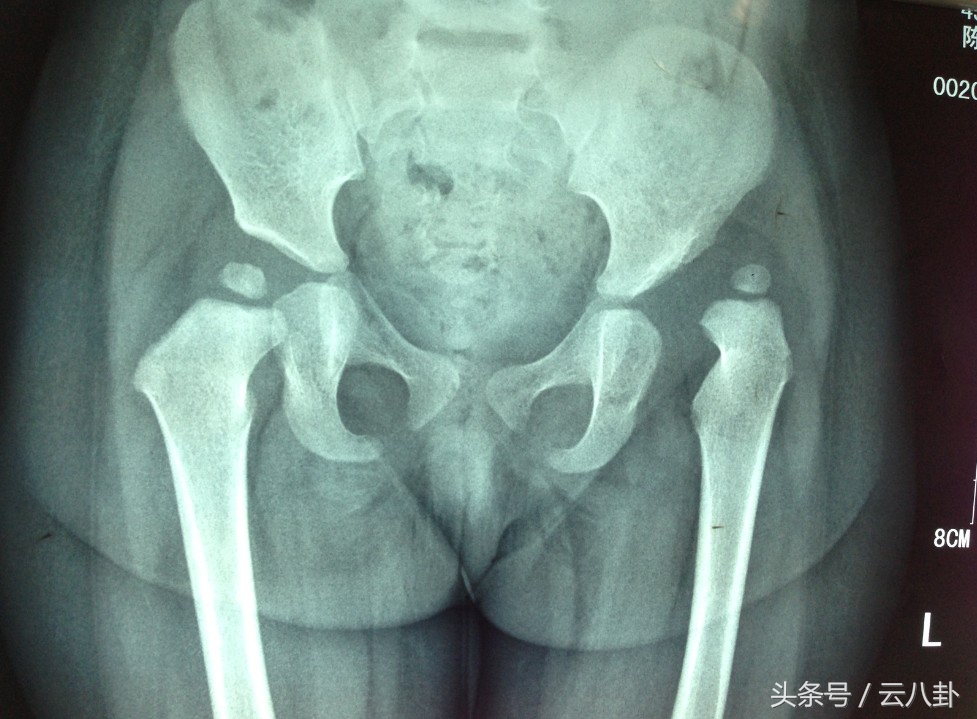

到医院时医生给孩子做了针对性骨科检查,拍片看髋臼是否有骨折?

经过检查分析,医生给赵女士讲孩子的情况,孩子是髋关节脱位,要及时给孩子做复位手术,只要麻醉下闭合整复就可以了。整复后要休息3-4周,避免患肢负重。